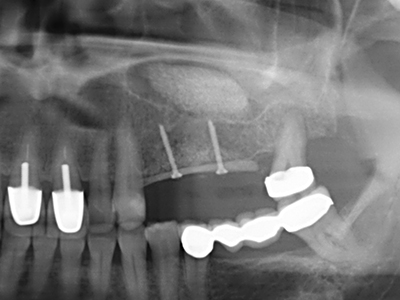

Fig. 11: The postoperative panoramic image shows the vertical augmentation and sinus floor elevation.

Fig. 12: After six months of healing, the alveolar ridge is vital and sufficiently dimensioned in all planes.

Fig. 13: Adequate irrigation with the 4-mm residual bone width is essential for this 52-year-old patient during the bone splitting.

Fig. 14: Placement of four tapered RSX implants (Bego Implant Systems, Bremen).

Fig. 15: The one-year follow-up x-ray examination shows stable conditions at the bone level.